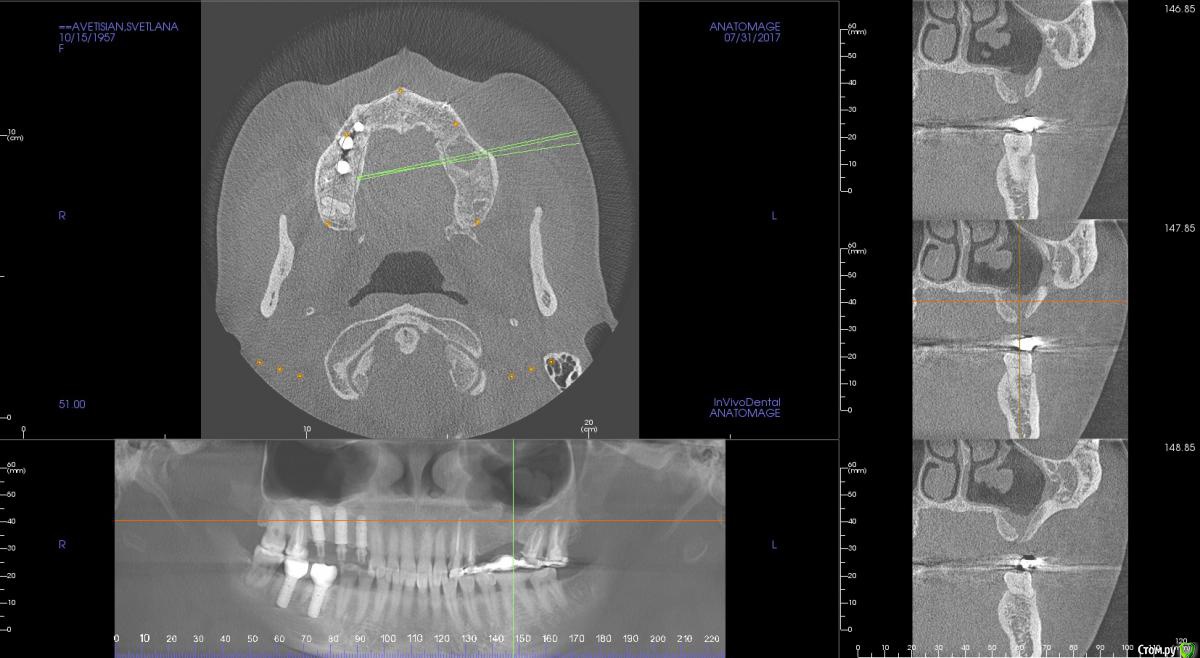

Тимур86 Опубликовано 31 июля, 2017 Поделиться Опубликовано 31 июля, 2017 10 лет назад был удален 26,после чего было 3 закрытия соустья и гайморотомии,какова тактика если синус делать? Ссылка на комментарий

kamranchick Опубликовано 31 июля, 2017 Поделиться Опубликовано 31 июля, 2017 10 лет назад был удален 26,после чего было 3 закрытия соустья и гайморотомии,какова тактика если синус делать?4-5-7 не вариант?)) и 8ку удалить к х*ям собачьим)) как раз без синуса)) и одномометно, ты Admetec попробовал? или я просто так тут жду?)) Ссылка на комментарий

kamranchick Опубликовано 31 июля, 2017 Поделиться Опубликовано 31 июля, 2017 Ну неужели своим обонянием не сможешь пациента убедить))На самом деле, ничего трудного нет... Остро надо отсепаровывать, и лучше закрытым идти.... И поставить 4.5 на 8.5 и все. Ссылка на комментарий

Bier Опубликовано 1 августа, 2017 Поделиться Опубликовано 1 августа, 2017 да тут все просто. расслоиться остро. немного поднять через соустье и потом сделать обычный латеральный доступ.Либо все поднять через соустье. 2 Ссылка на комментарий